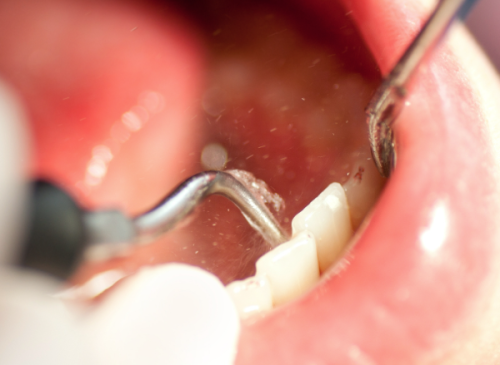

即刻种植:采用从德国引进的舒适化微创技术,手术精细定位,创口小、出血少,能在短时间内为患者植入种植体,快速修复牙齿外观与部分咀嚼功能,减少患者等待时间与术后不适感。

微创种植:以患者舒适为核心,运用精良的微创诊疗设备,尽可能缩小手术创口,降低手术对口腔组织的损伤,术后修复快,同时确保种植体的稳定性与成功几率,满足患者对美观与功能的需求。